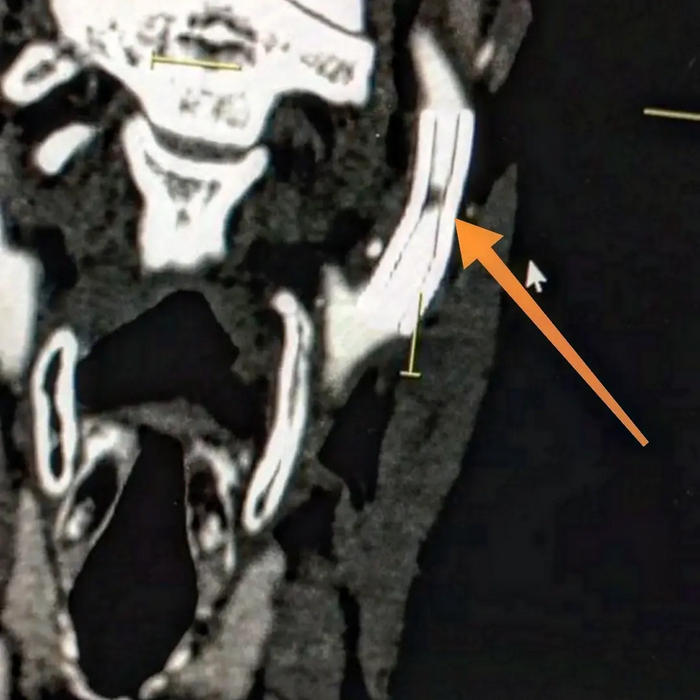

Делает ВСУЗИ (внутрисосудистое ультразвуковое исследование = специальный датчик заводится в сосуд через катетер и он изнутри датчик сканирует сосуд ультразвуком, в нашем случае частотой 40 Мгц)

Картина на ВСУЗИ:

Выявлена в начальном сегменте ПМЖА большая нестабильная атерома (желтым) с липидным ядром с распадом, на устье ПМЖА уже сформирована фиброзная атеросклеротическая бляшка (красным) с переходом на ствол левой коронарной артерии. Сама артерия по ВСУЗИ большая